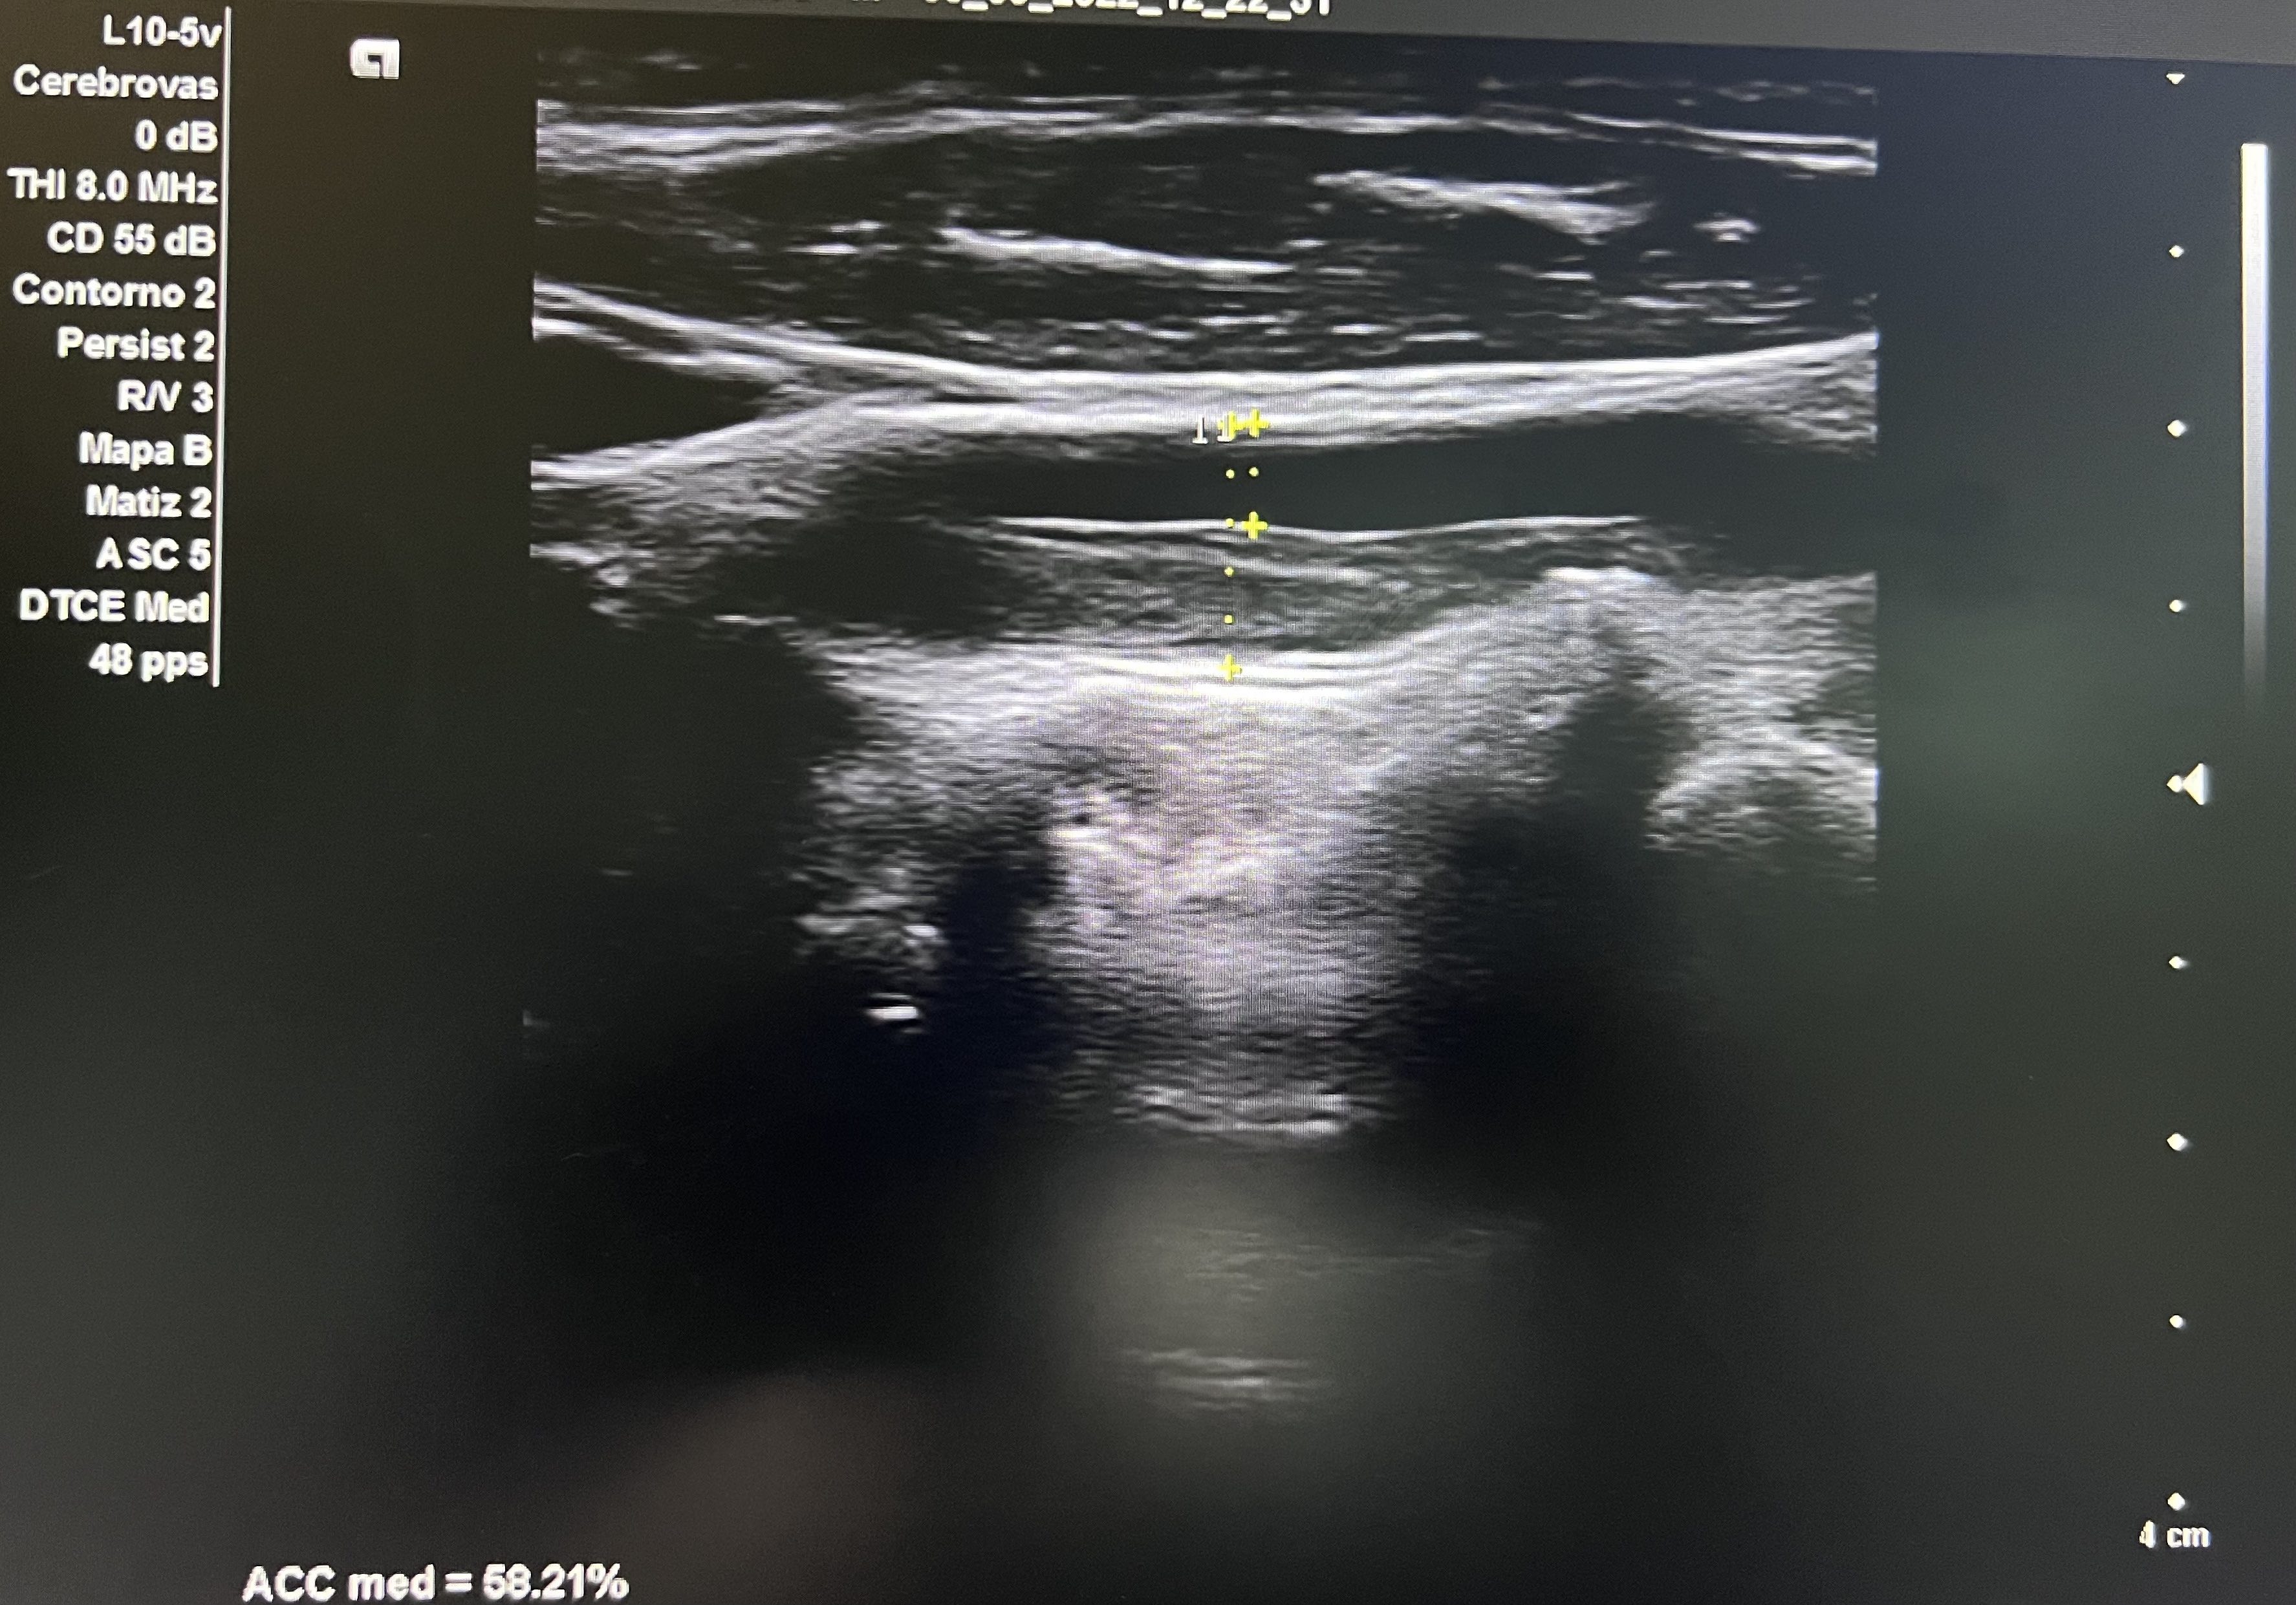

Hallazgos ecográficos

Aorta abdominal de calibre normal. Arteria carótida derecha sin lesiones. En arteria carótida común izquierda se observa placa longitudinal desde porción media hasta proximal que obstruye un 58% en su diámetro máximo.